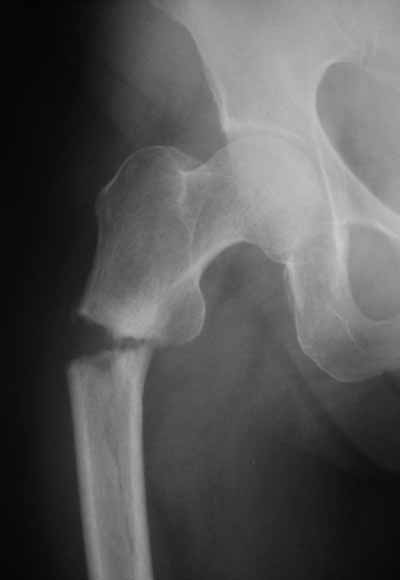

> > Я имею ввиду довольно редкий простой поперечный перелом на 1-2 см

> > ниже малого вертела.

>

> Тут шеечный винт Не фиксировал бы периферический отломок, так что

> конечно, дистальный винт был бы нужен. Хотя для такого перелома вообще

> короткий штифт какой-то неуютный выбор.

Не думаю так. см вложение.